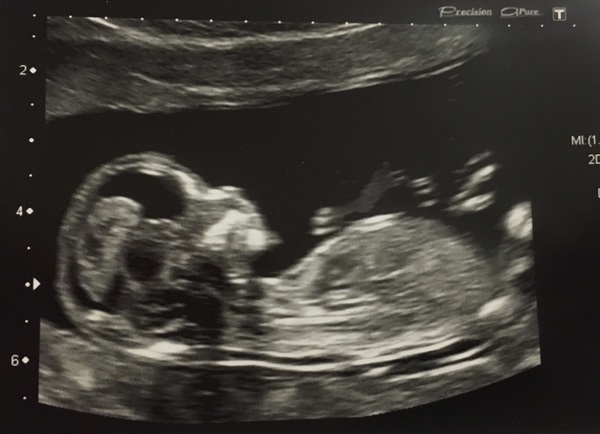

lucieloos · 15/11/2016 13:40

Mine went well too although such a naughty baby we had to go in and out 3 times as it was wriggling so much and doing handstands and in every position apart from the one she needed! I'm still measuring 5 days ahead so am now officially 13w2d instead of 12w4d and my due date has been put forward to 21st may from 25th. She eventually managed to measure the nuchal which was 1.8mm so all good. Got a consultant appt booked in for 16 weeks for them to assess if I'm to be midwife or consultant led and then 20 week scan on 3rd Jan! Such a relief to get all that done and we can now start to tell people!